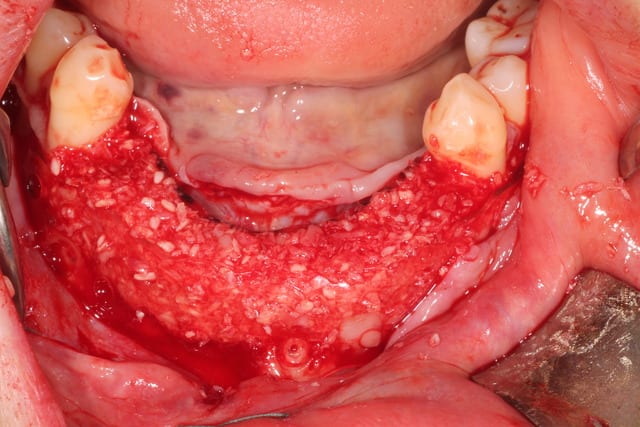

Bon, finalement, j'ai fait comme ça :

Oui, c'est bien en boxtechnique. J'ai fait une formation en avril dernier avec Andrea Menoni , initiateur de la technique en 2008. Je pense poursuivre à parme en octobre.

j'ai donc utilisé comme Maximini du MinerOss cortical-spongieux + autogene + prf + metro.

recouvert de prf, d'une membrane jason pericadium et de prf.

plaque resorb X , 0.8 mm, 11x126 mm : 235 €

5 pins : 350 €

MinerOss : 2.5 +1 cc : 360 €

Jason 4x3 : 180 €

Total : 1120 : oups, devis 1280 ! 3 heures !

Sur la video , il y a les deux techniques pour donner de la flexibilité au lambeau : technique Andréa avec le décolleur en lingual, et Maximini avec le Metzenbaum en vestibulaire.